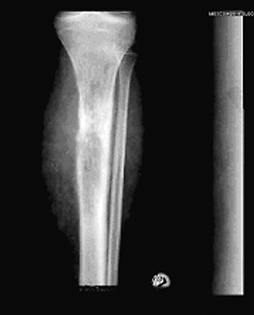

После курсов полихимиотерапии следует радикальное хирургическое лечение. При локализации опухоли в длинных трубчатых костях и небольших ее размерах могут производиться органосохраняющие операции в объеме резекции суставного конца или тотальное удаление длинной трубчатой кости с эндопротезированием (рис. 2). При опухолях с большим внекостным компонентом показана ампутация (экзартикуляция) на уровне вышерасположенного сегмента конечности. Для уточнения степени распространенности опухолевого процесса используются КТ и МРТ, а также планарная сцинтиграфия.

Рисунок 2. Остеосаркома бедренной кости:

а — до операции; б — после операции